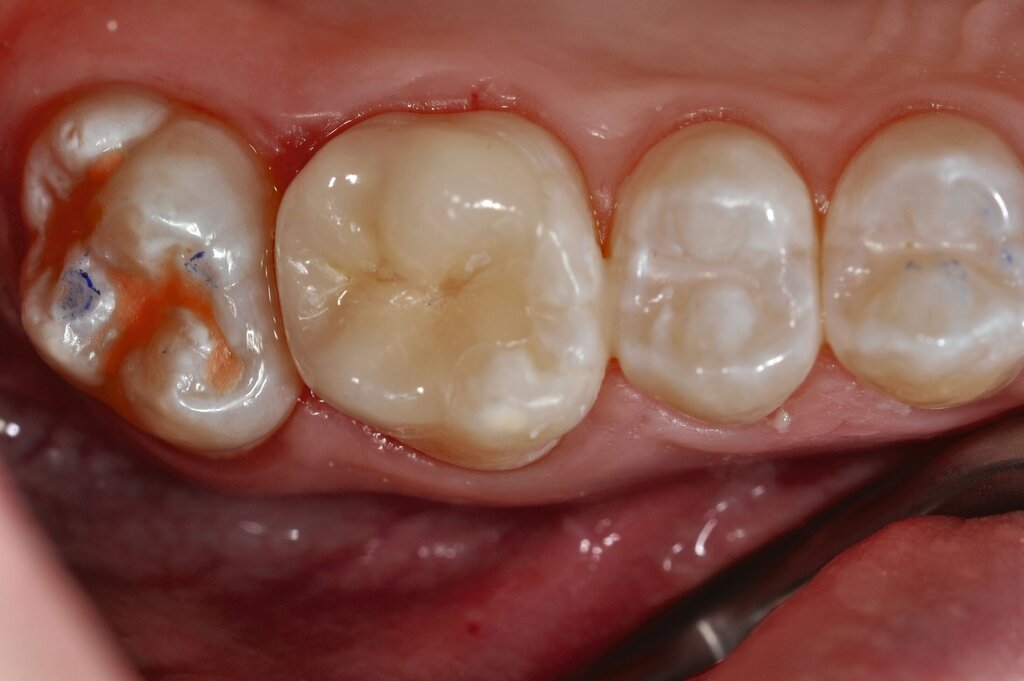

Die direkte Versorgung mit Komposit hat den Vorteil, dass durch die Verwendung von Dentinadhäsiven das Dentin dicht versiegelt werden kann. Hypersensitivitäten werden dadurch deutlich reduziert. Zudem kann der Zahn bei der direkten Versorgung sehr defektorientiert versorgt werden (Abbildung 7).

Während die Dentinhaftung unterhalb des affektierten Schmelzes vergleichbar mit der von gesundem Dentin ist, funktioniert die Haftung an dem strukturell veränderten Schmelz schlechter. Eigene Untersuchungen haben gezeigt, dass die Haftung an dem porösen, proteinreichen Schmelz stark reduziert ist (Abbildung 8) [Krämer et al., 2018]. Sind die Füllungsränder in dem veränderten Bereich lokalisiert, muss mit Randspalten und Abplatzungen gerechnet werden.

Bei größeren Restaurationen muss man im Laufe der Jahre mit Verfärbungen der Füllungen und mit Abrasionen rechnen. Dies spielt insbesondere eine Rolle, wenn im Seitenzahnbereich Höcker ersetzt werden müssen, da Kompositfüllungen mit Höckerersatz an MIH-Molaren eine etwas geringere durchschnittliche Überlebenszeit in der Mundhöhle haben als solche ohne Höckerrekonstruktion [Rolim et al., 2021].